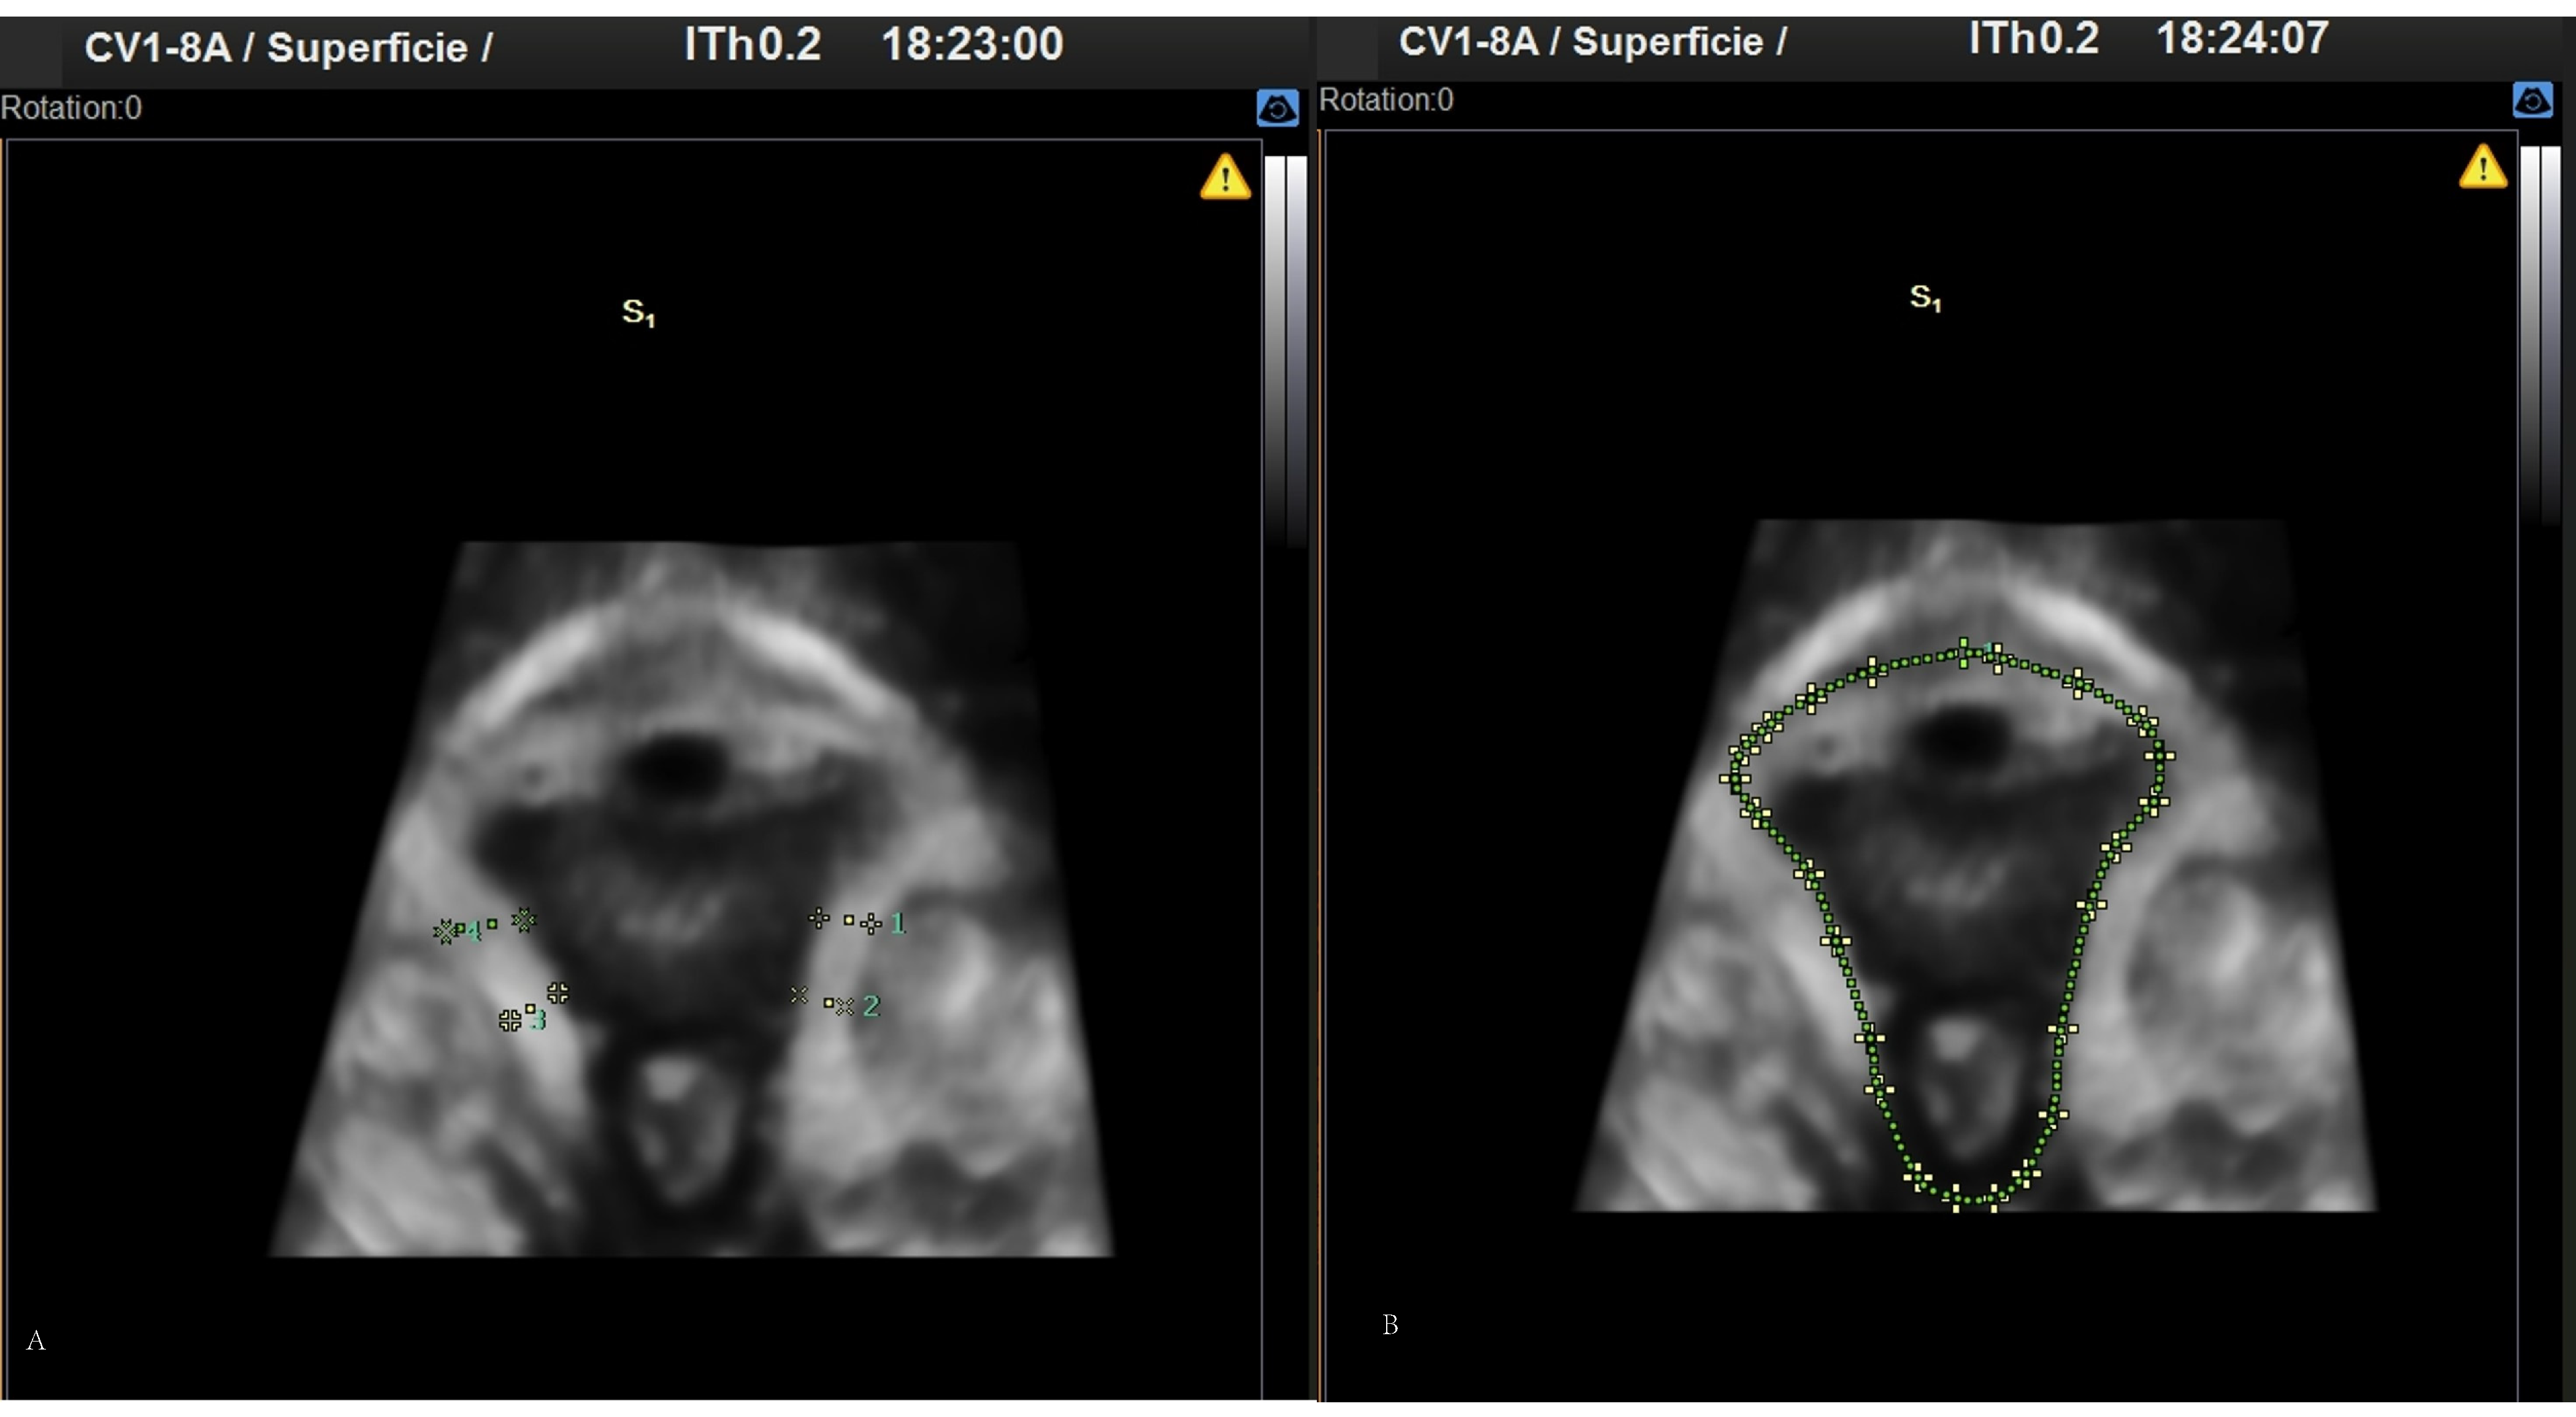

Figure 2.

3D images obtained by perineal ultrasound. (A) Pubovisceral muscle thickness. (B) Perineal hiatus area.